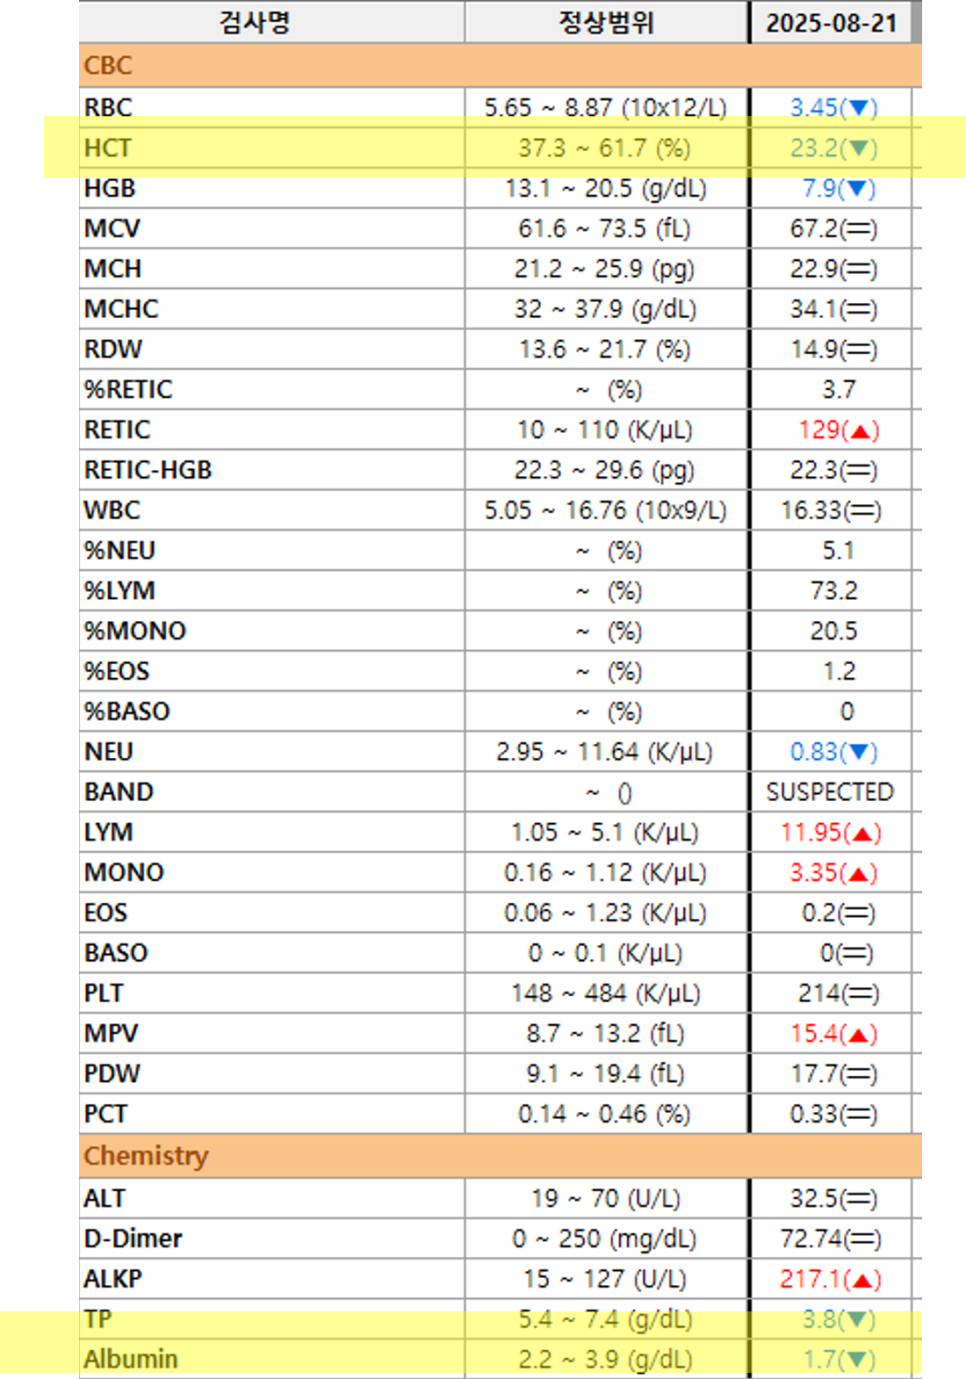

검사 결과

HCT 수치의 현저한 저하와 총 단백질, 알부민 수치의 동반 저하가 확인되어 출혈로 인한 재생성 빈혈로 진단되었습니다.